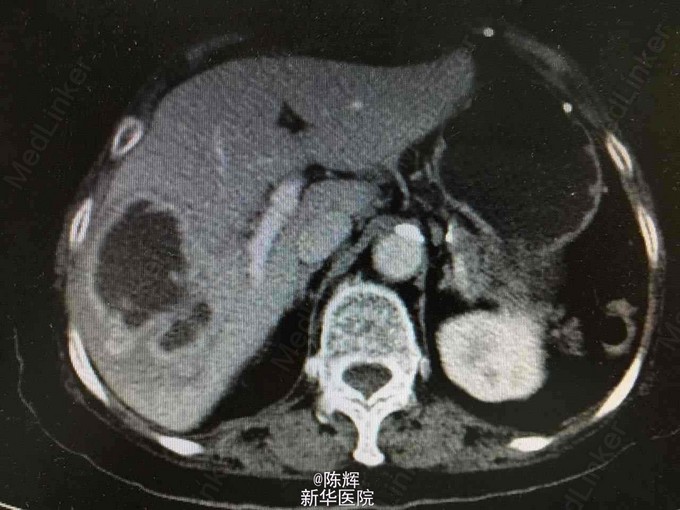

患者,女,82岁 主诉:患者无明显诱因下出现寒战,高热,体温高达41度,热型无规律,伴纳少,乏力。无腹痛、腹胀等不适。 查体:心前区无异常隆起,心率78次/分,律不齐,可闻及早搏3次/分, 心音可,未及额外心音,各瓣膜区未及病理性杂音,未及心包摩擦音。腹平软,无压痛、反跳痛及肌卫,肝脾肋下未及,移动性浊音(-),肠鸣音正常。 胸部CT平扫:右肺下页及左肺胸膜下条索影,右肺下叶背段点状钙化灶,右侧胸膜局部钙化上腹部MR平扫+增强:肝脓肿。左肾盂积水,两侧少量胸腔积液。 血常规:白细胞计数 5.50 10^9/L,红细胞计数 3.86 10^12/L|血红蛋白 123 g/L,血小板计数 163.00 10^9/L ,肝功能:谷丙转氨酶(干片法) 673.0 u/L 谷草转氨酶(干片法) 601.0 u/L|总胆红素(干片法) 196.4 umol/L 诊断:肝脓肿 治疗经过:行超声引导下肝脓肿穿刺抽液术,并留置引流管。5天后复查肝脏B超提示脓肿明显好转,予以拔除引流管。目前患者无发热,无腹痛等不适,一般情况可,予以出院。 总结:三个月后随访主诉症状好转,高龄老年患者如出现肝脓肿,还是尽早行穿刺引流,避免出现全身的脓毒血症.